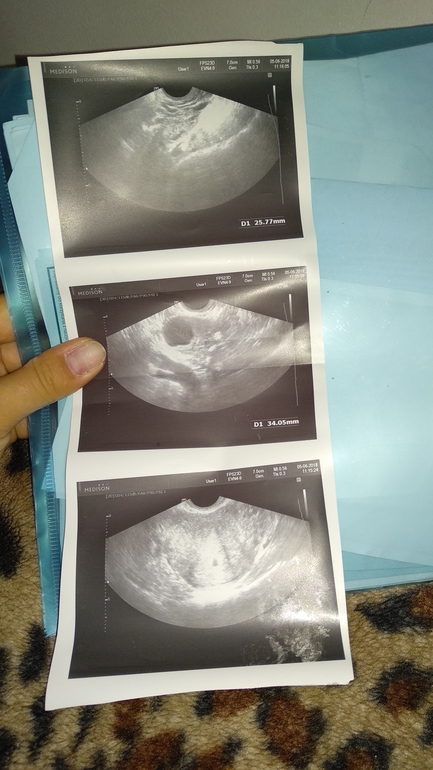

Девочки,что скажете.по месячным сегодня 5недель и 1деньбеременности . овуляция поздняя на 18д.ц. Хгч на 17дпо 1177.есть некоторые выделения,пью Дюфастон по 1/2раза,магний.свкчи папаверина,фолька.Больше года назад была анэмбриония.Чистка.сегодня врач посмотрела на УЗИ,потому что мазалось .в итоге,сказала,что пя видно,но не такое как хотелось бы.и эмбриона тоже нет.Контроль хгч и УЗИ через 2недели.Очень боюсь.Неужели повторная анембриония..может кто понимает эти картинки..нормально ли жт ...расстроилась.и не спросила..и врач тоже была обеспокоена

Спасибо,а что скажете про жт ?там указаны размеры...а на первой картинке это толщина эндика?